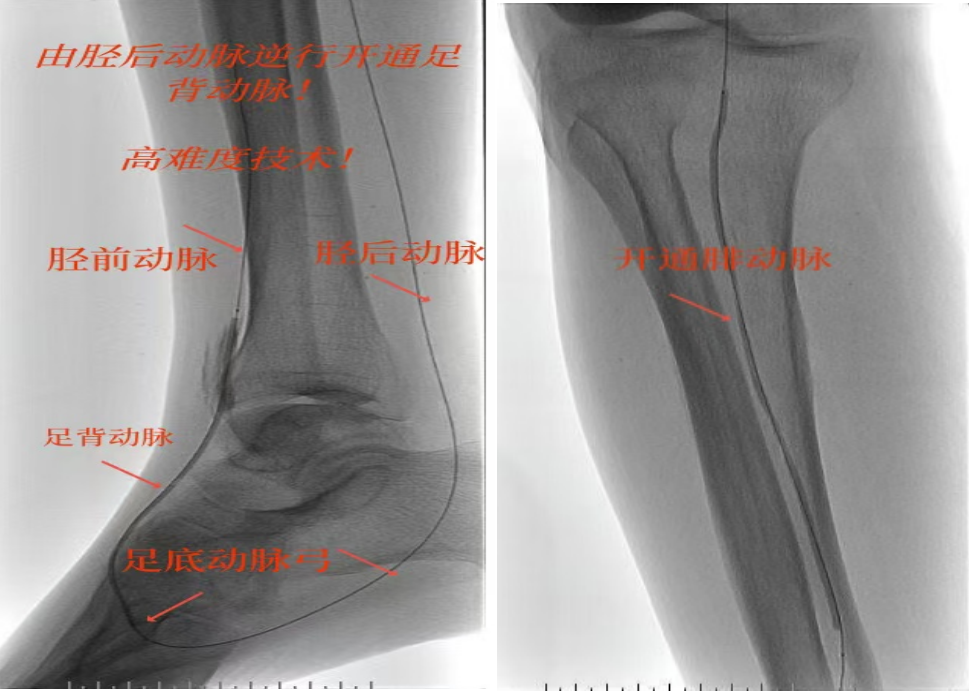

78岁男性患者,糖尿病合并高血压、脑梗塞,右足持续疼痛伴冰凉发绀3个月。入院CTA显示其右侧股浅动脉全程闭塞,膝下三支动脉均闭塞。医疗团队在局部麻醉下,再次巧妙应用“逆向开通技术”,经胫后动脉——足底弓逆向开通足背动脉及胫前动脉。术后患者右足皮温即刻回升,疼痛消失。术后结合中药外治(换药、熏洗、去腐生肌膏外敷)加速创面愈合,患者已顺利出院。

影像检查:CTA显示右侧股浅动脉全程闭塞,膝下三支动脉(胫前、胫后、腓动脉)完全闭塞。

两例患者共同凸显三大高难度治疗挑战:1.患者高龄且基础病复杂;2.血管全程多节段闭塞、钙化程度严重;3.常规顺向开通路径已被完全阻断。团队果断采用远端逆行穿刺技术,在纤细的足踝部血管建立治疗通道,实现“逆向破冰”。

“逆向开通操作技术”就像在复杂的血管迷宫中反向找“出口”。介入血管外科杨彦林副主任形象地比喻道,“该操作技术突破了传统顺向开通的技术局限,为濒临截肢的晚期糖足患者提供了宝贵的保肢新选择。”目前该方案已成为我院治疗复杂下肢动脉病变的常规手段。